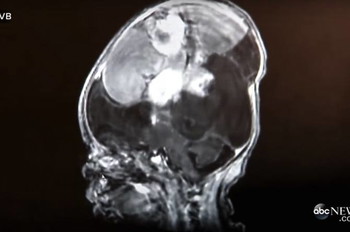

According to the doctors, the mass in her brain was huge, aggressive and malignant, which meant it was only going to get bigger. She would be too small for chemotherapy and the cancer would only return if they operated.

But at Erika’s 30-week ultrasound, doctors found the large tumor inside her brain.

A new brain scan and the new doctor’s opinion revealed that the tumor could actually be removed and wasn’t even cancerous!

The doctors successfully extracted all of the brain mass. Dr. Cohen said the growth in her brain would probably not return.